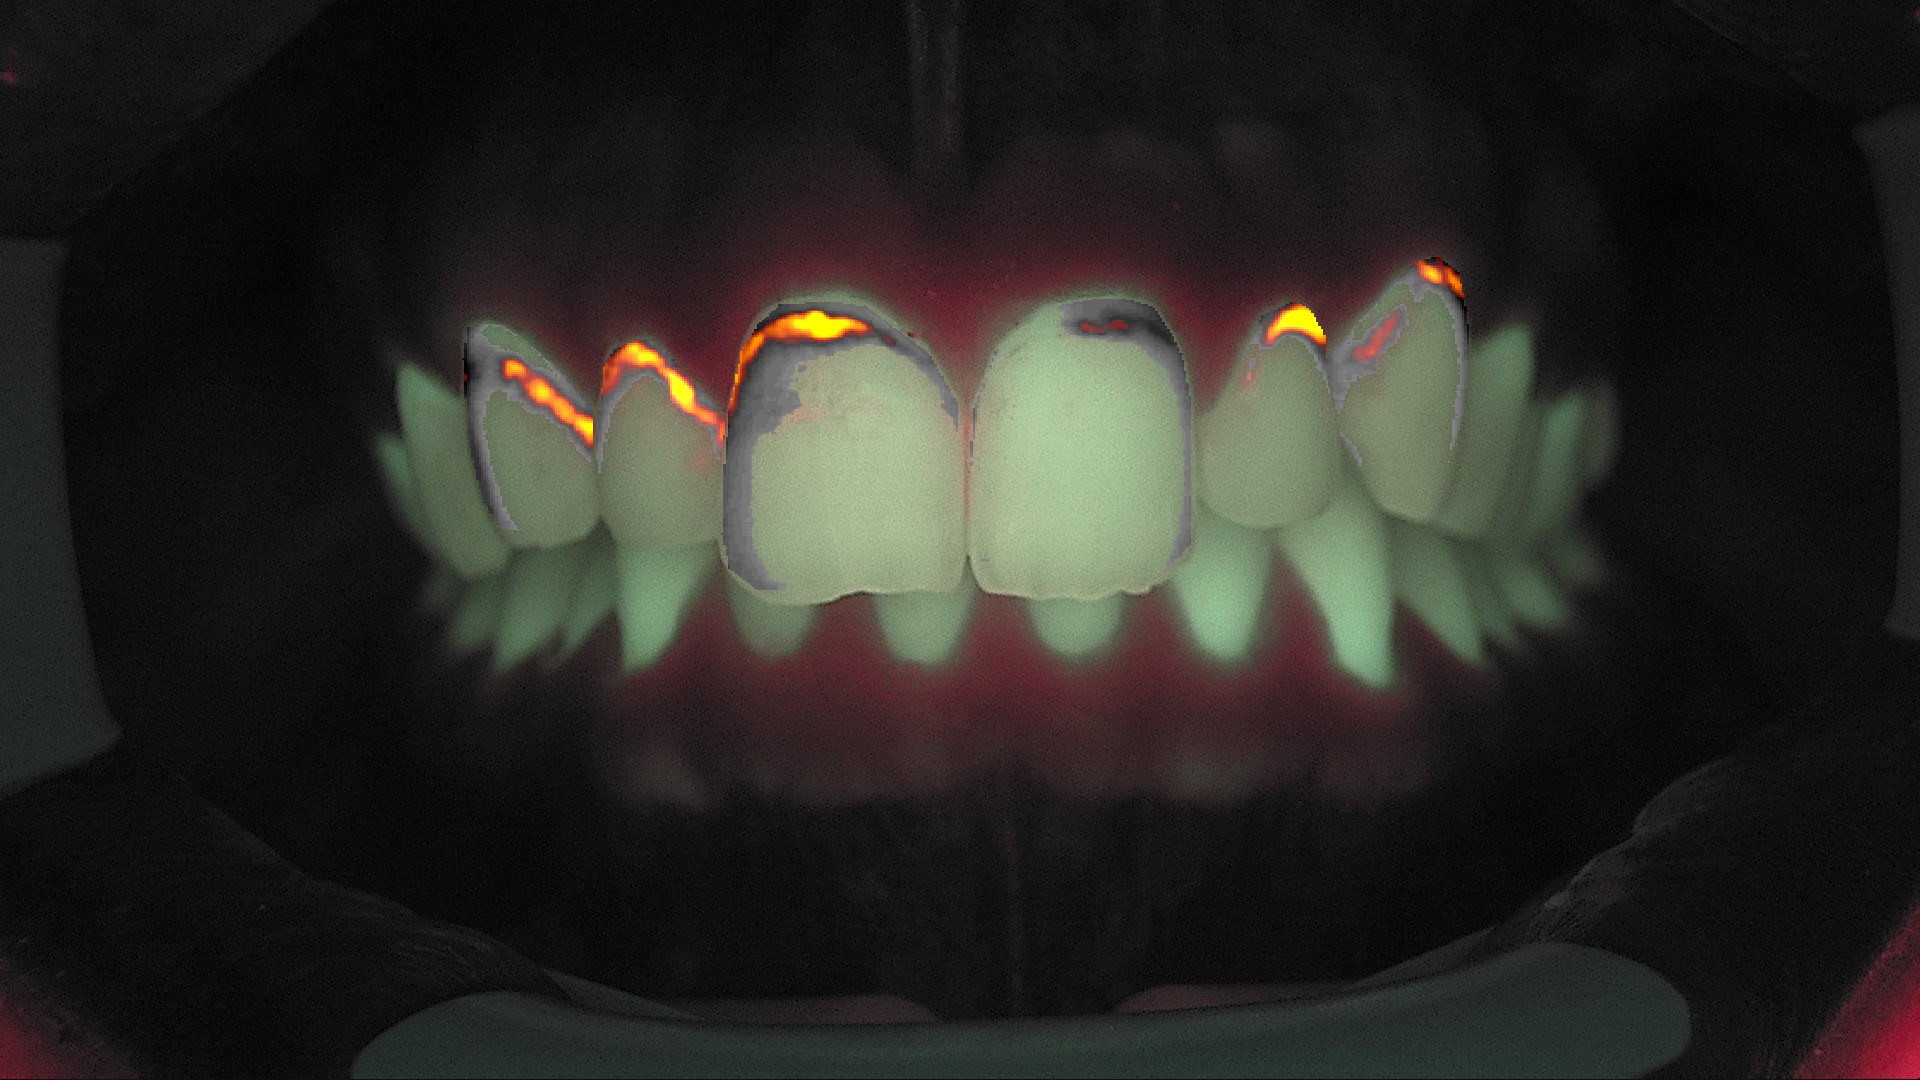

Fig. 3B - Fluorescenza immediata post-trattamento: ΔF ridotto a circa –13,4%, segno di saturazione dei micro-pori.

La nuova acquisizione con QrayCam Pro mostra valori ΔF compresi tra –6,2% e –8,5% e una ulteriore riduzione dell’area di white spot a meno di 200 px², a conferma di una stabilizzazione del risultato.

La resina infiltrante consente una gestione minimamente invasiva delle white spot, il principio è ben noto e con un duplice beneficio: arresto o rallentamento della progressione della lesione e miglioramento estetico legato alla riduzione del contrasto ottico. Nel caso descritto, la sola infiltrazione ha determinato il passaggio da ΔF fortemente negativi (–47,8/–56,1%) a valori prossimi alla normalità (–6,2/–8,5%) già al primo mese.